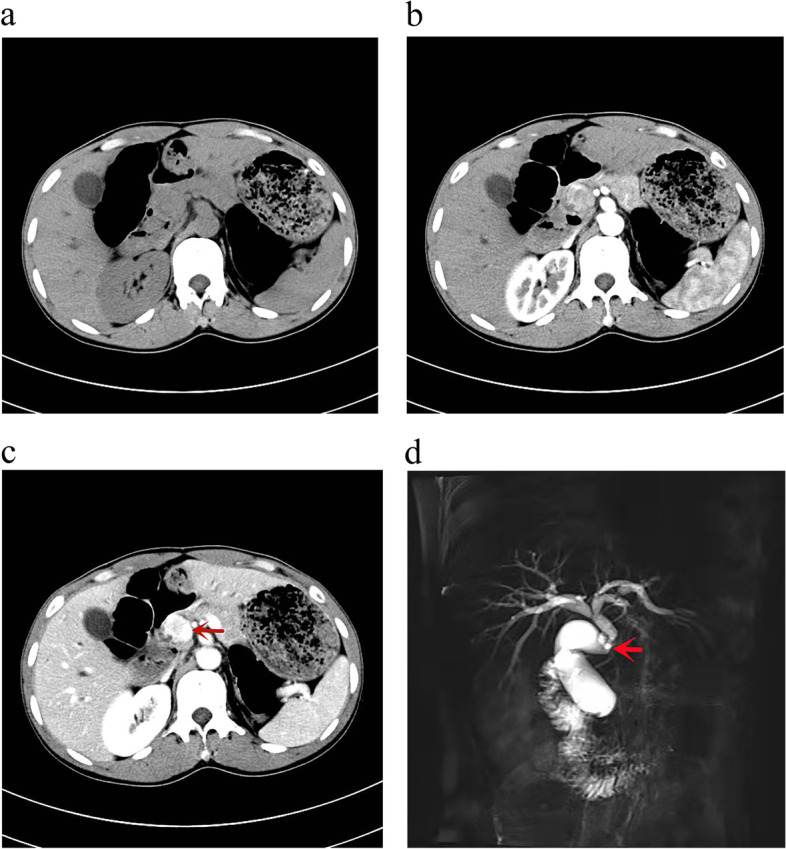

We present the case of a 34-year-old male with no relevant medical history who presented with jaundice of 20 days of evolution. His examination revealed scleral and whole-body skin icterus. There was no abdominal tenderness, rebound tenderness, and the Murphy test was negative, with no palpable mass. There was no evidence of any other organomegaly or lymphadenopathy. His test results on admission were as follows: total bilirubin, 5.17mg/dl; direct bilirubin, 2.49 mg/dl; alkaline phosphatase, 152 U/L; and CA199, 58.5 U/ml. Viral serological tests for hepatitis A, B and C and HIV were negative. Computed tomography (CT) revealed the following: soft tissue nodules in the CBD with clear borders, inhomogeneous morphology, heterogeneous density, equal or slightly low-density changes and nodules bulging into the lumen of the CBD. In the venous phase, there was significant heterogeneous enhancement, which was more obvious than that in the arterial phase and showed gradual strengthening changes (Fig. 1a–c). Magnetic resonance cholangiopancreatography revealed a localized filling defect in the lower part of the CBD with luminal narrowing (Fig. 1d). The patient was evaluated by a multidisciplinary committee. The clinical diagnosis was obstructive jaundice with the possibility of bile duct cancer. Laparoscopic pancreaticoduodenectomy was performed. Intraoperatively, adhesions of the omentum and abdominal wall were observed, no ascites were observed in the abdominal cavity and severe cholestasis was observed in the liver. A mass approximately 1.5 × 1.5 cm in size was detected in the lower segment of the CBD. The gallbladder, duodenum, part of the stomach, CBD and head of the pancreas were removed. The bile duct and jejunum were anastomosed, the jejunum and pancreas were anastomosed and a silicone stent and drainage tube were placed. No biopsy was taken during the operation, and there was no biliary leakage.